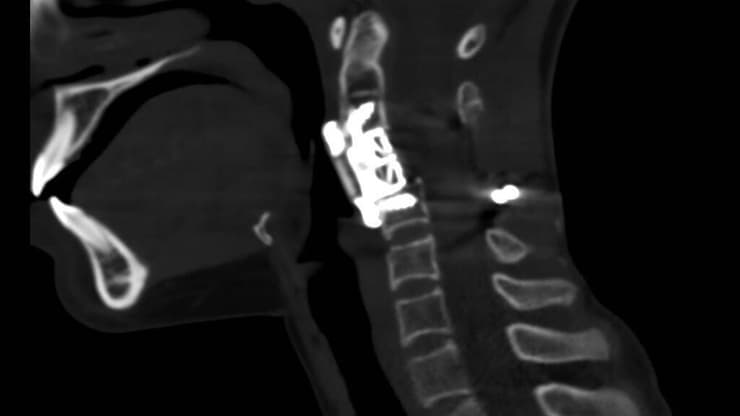

בצילום CT זה נראית החוליה המלאכותית שהושתלה במקום החוליה הנגועה שהוסרה בשלמותה

(צילום הדמיה: באדיבות פרופ' צבי לידר)

מבלי להיכנס לתוכה ובזהירות רבה פעלו המנתחים מעליה ומתחתיה. "ואחרי שהפרדנו שרירים ושרשרות עצבים, החוליה השתחררה ב-360 מעלות וכרתנו אותה בשלמותה. במקומה השתלנו חולייה חליפית עשויה מחומר ידידותי לגוף האדם, על פי מידותיה של שני שנלקחו עוד לפני הניתוח".